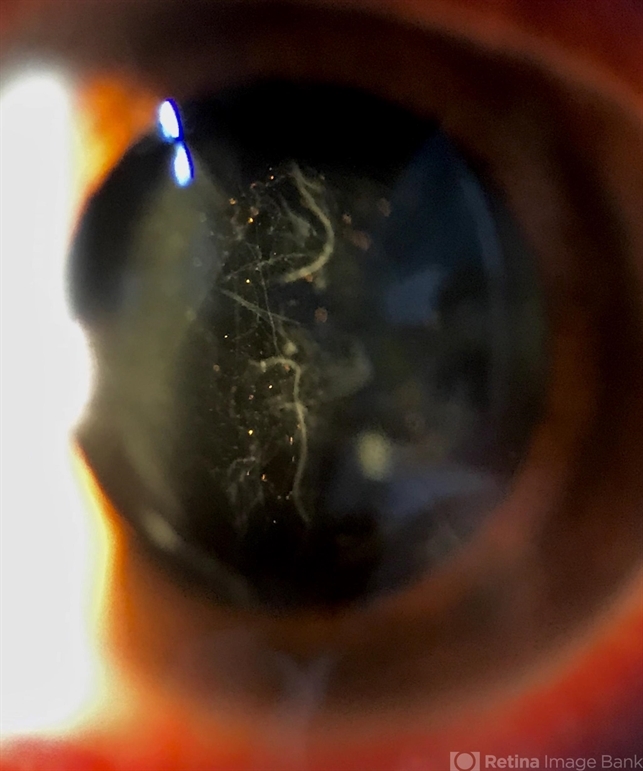

- Slit lamp photograph of a 58-year-old man with rhegmatogenous retinal detachment and tobacco dust presence.